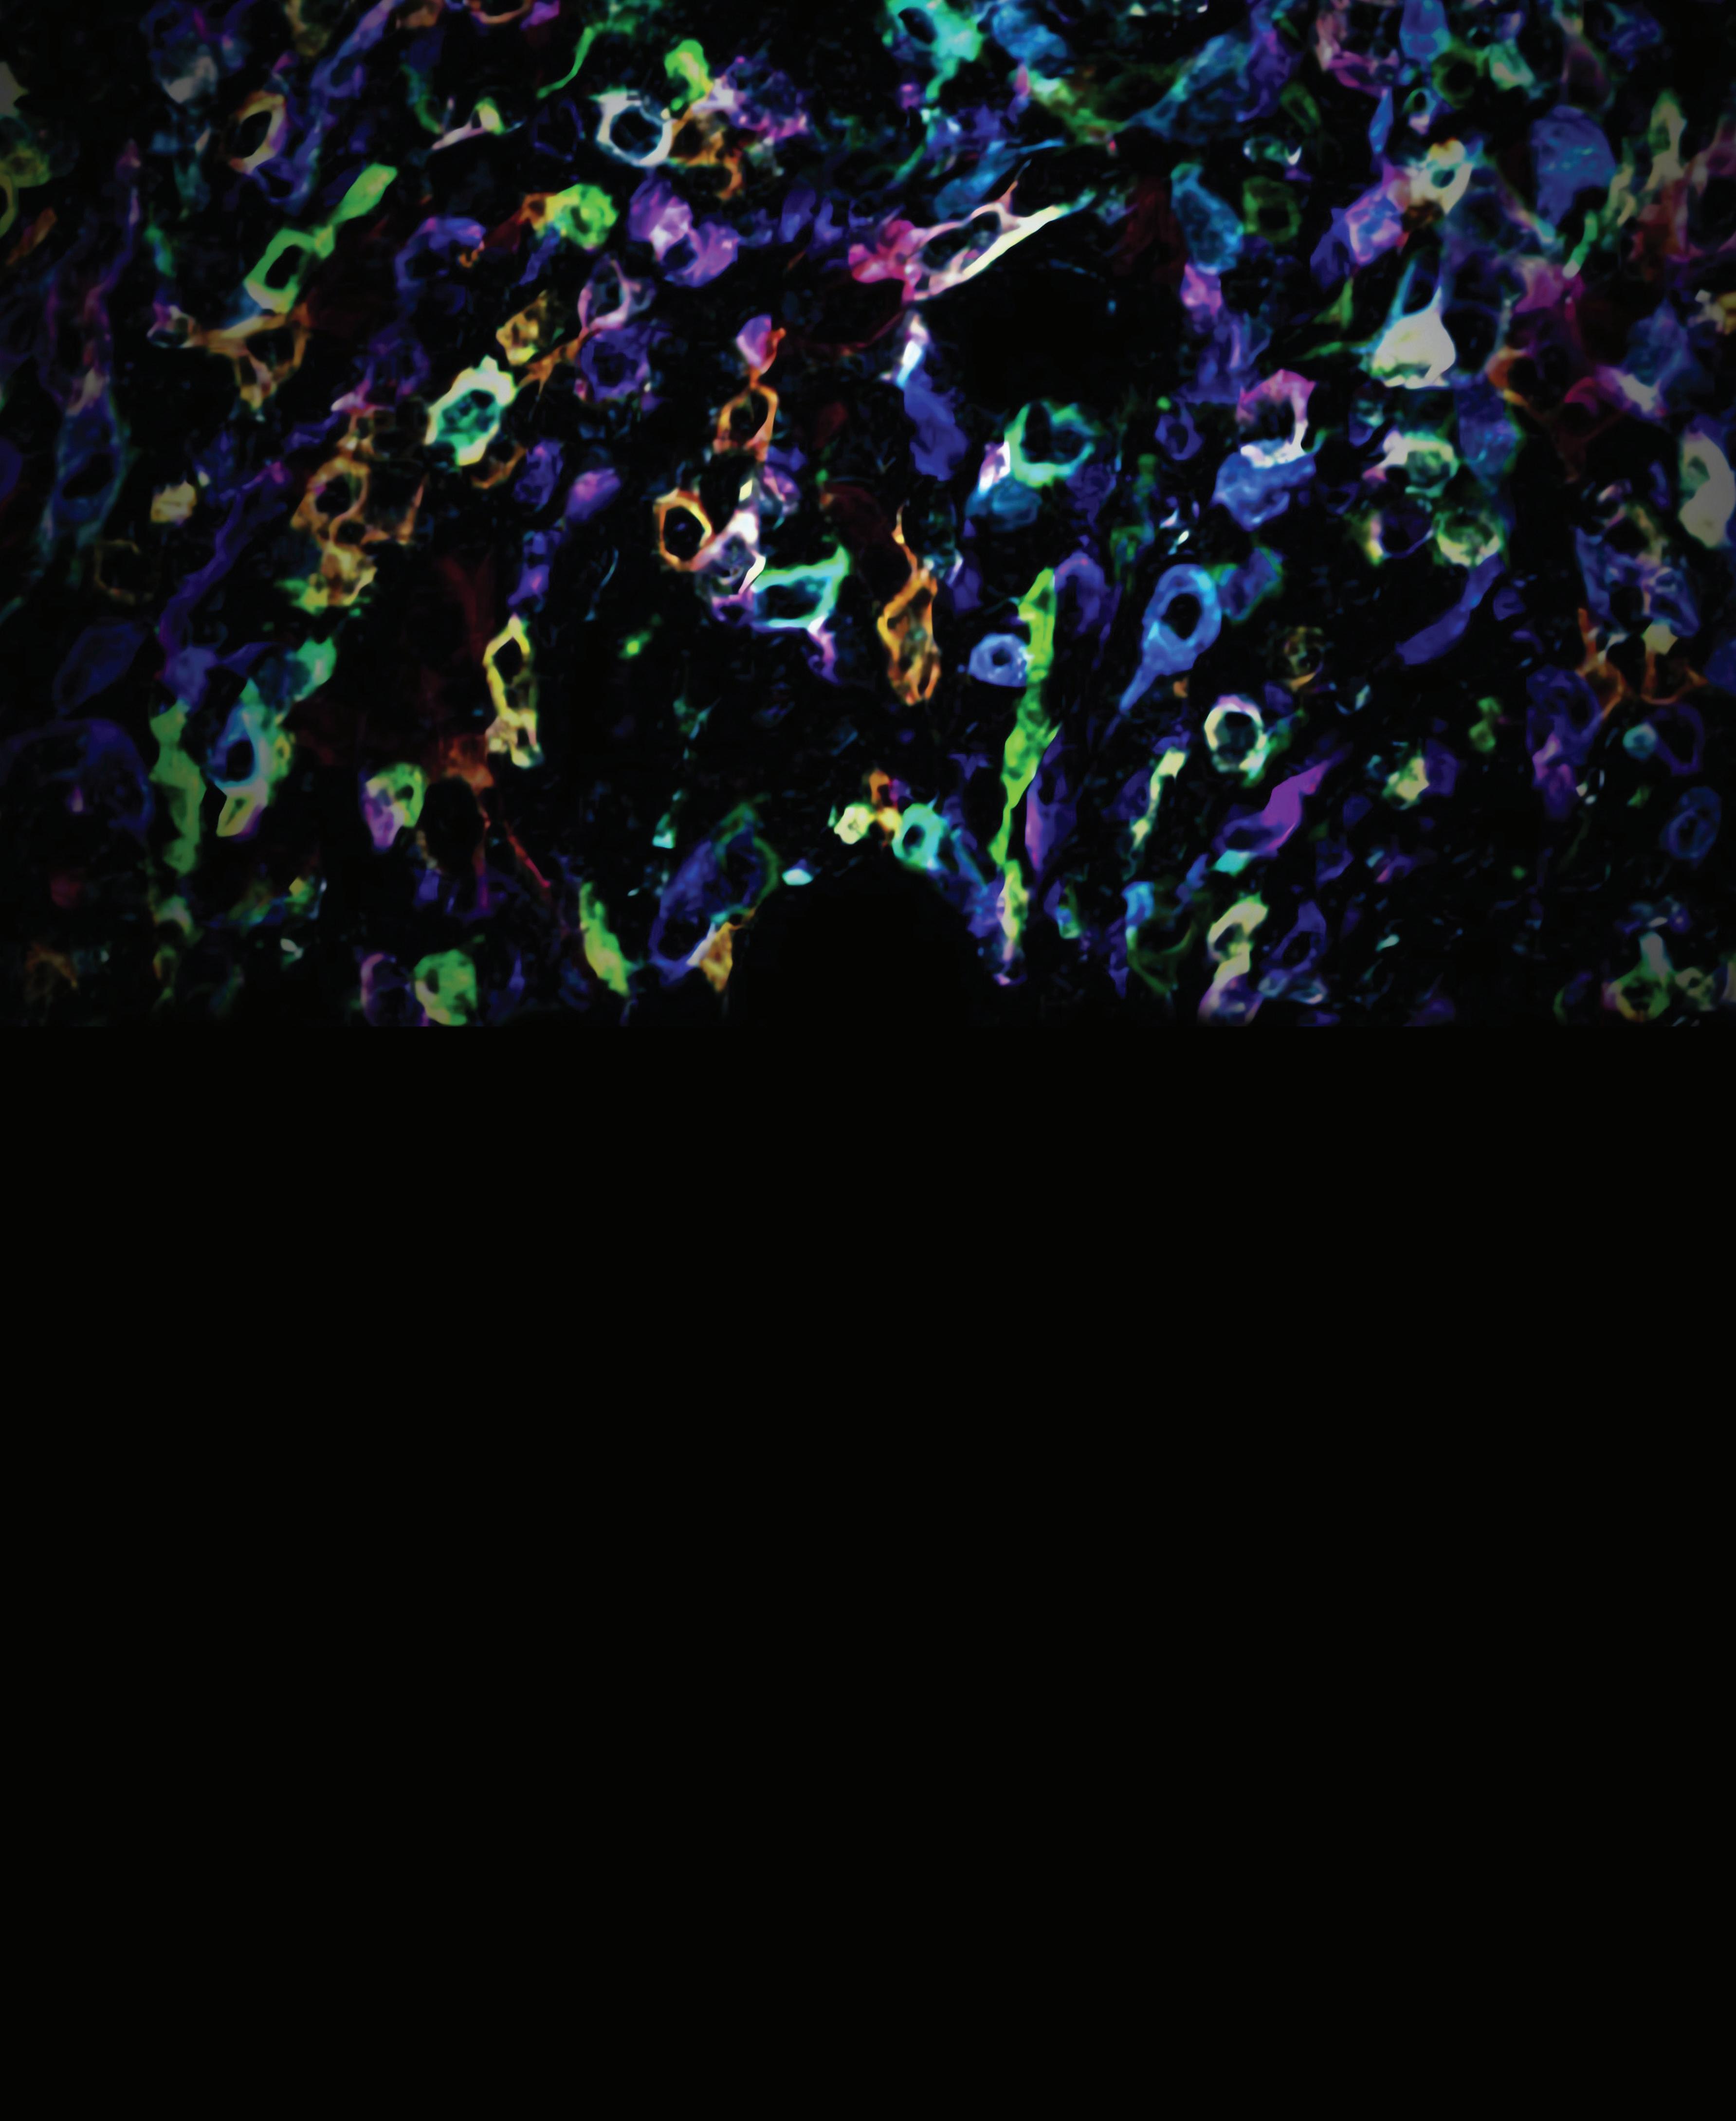

The new interdisciplinary departments at the Icahn School of Medicine at Mount Sinai are bringing innovative thinking to the challenges of preventing and treating disease. Recognizing the importance of the immune system’s influence on the entire human body, we have established the Department of Immunology and Immunotherapy. In collaboration with the Icahn Genomics Institute, the Department’s researchers are developing advanced gene and cell engineering technologies to study immune function, with a particular focus on understanding how cancer impairs the body’s natural defenses.

Chair, Department of Immunology and Immunotherapy; Director, Marc and Jennifer Lipschultz Precision Immunology Institute; Director, Human Immune Monitoring Center; Mount Sinai Professor, Cancer Immunology

In her new role as Dean for Translational Research and Therapeutic Innovation, Miriam Merad, MD, PhD, aims to elevate early clinical trials at Icahn Mount Sinai, streamline the clinical trial process, cultivate a culture of mechanistic clinical trials throughout the campus, and forge stronger partnerships with the pharmaceutical and biotech sectors.

A world-renowned immunologist, Dr. Merad has spent years investigating the potential for new therapies to treat cancer and inflammatory diseases, and her work has made Mount Sinai one of the most advanced centers in the world for immunological research.

In 2020, Dr. Merad was elected to the National Academy of Science for her transformational discoveries, establishing for the first time the tissue-resident macrophage lineage and revealing its key contribution to tissue health, repair, infection defense, and impact on tumor outcomes. Her research led to the identification of new therapeutic targets and was published in more than 300 highprofile papers and cited 1,000 times.